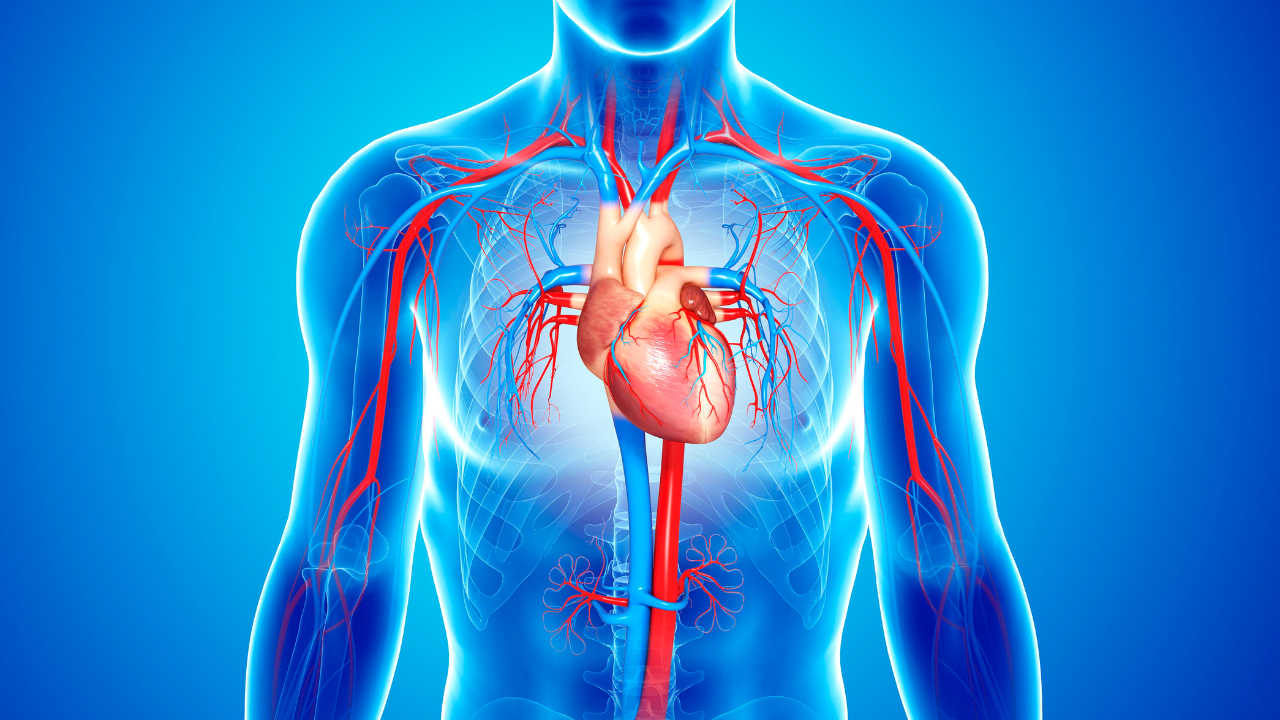

Cardiovascular disease (CVD) continues to be the number one cause of death worldwide, with its impact escalating in aging populations. Although medical interventions have significantly advanced to lower risk, an expanding amount of research emphasizes the role of dietary components in influencing cardiovascular outcomes. Of these, vitamin K₁ (phylloquinone), which is present abundantly in leafy green vegetables, has appeared as a salient, yet overlooked nutrient for cardiovascular well-being.A recent longitudinal study that appeared in The American Journal of Clinical Nutrition (2025) shed new light on this relationship, the sweet-sour relationship between leafy greens and our taste buds. The researchers observed 1,435 community-living women aged more than 70 for over 14 years to assess the effect of sustained vitamin K₁ consumption on vascular morphology and cardiovascular death. The results are both interesting and of clinical significance.

Vitamin K₁ has an important function in the activation of matrix GLA protein (MGP), an important inhibitor of vascular calcification. In the absence of the very essential nutrient vitamin K₁, MGP is inactive, and calcium deposits in arterial walls lead to stiffness and atherosclerotic plaque formation. This action has been understood to be at the center of both coronary artery disease and cerebrovascular diseases, such as stroke.

The study: Lower Arterial thickening and mortality

In the above-mentioned study, volunteers were divided into quartiles based on their dietary vitamin K₁ consumption. Subjects in the upper intake quartile (~120 μg/day) had:

- A 5.6% smaller carotid intima-media thickness (IMT), a well-established marker of subclinical atherosclerosis, than those in the lowest quartile

- A 43% reduced risk of cardiovascular disease death, adjusted for variables such as age, BMI, physical activity, medication use, and smoking status